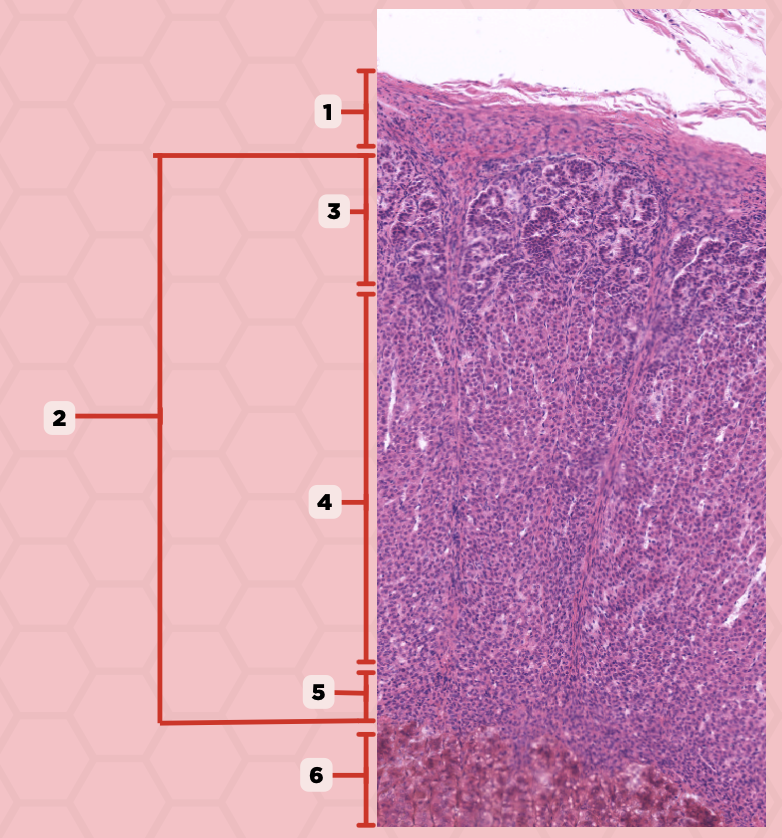

Pituitary

Identify the specimen.

Anterior Lobe

Identify the structure labeled as 1.

Posterior Lobe

Identify the structure labeled as 2.

Intermediate Lobe

Identify the structure labeled as 3.

Pars Tuberalis

Identify the structure labeled as 4.

Pituitary Stalk

Identify the structure labeled as 5.